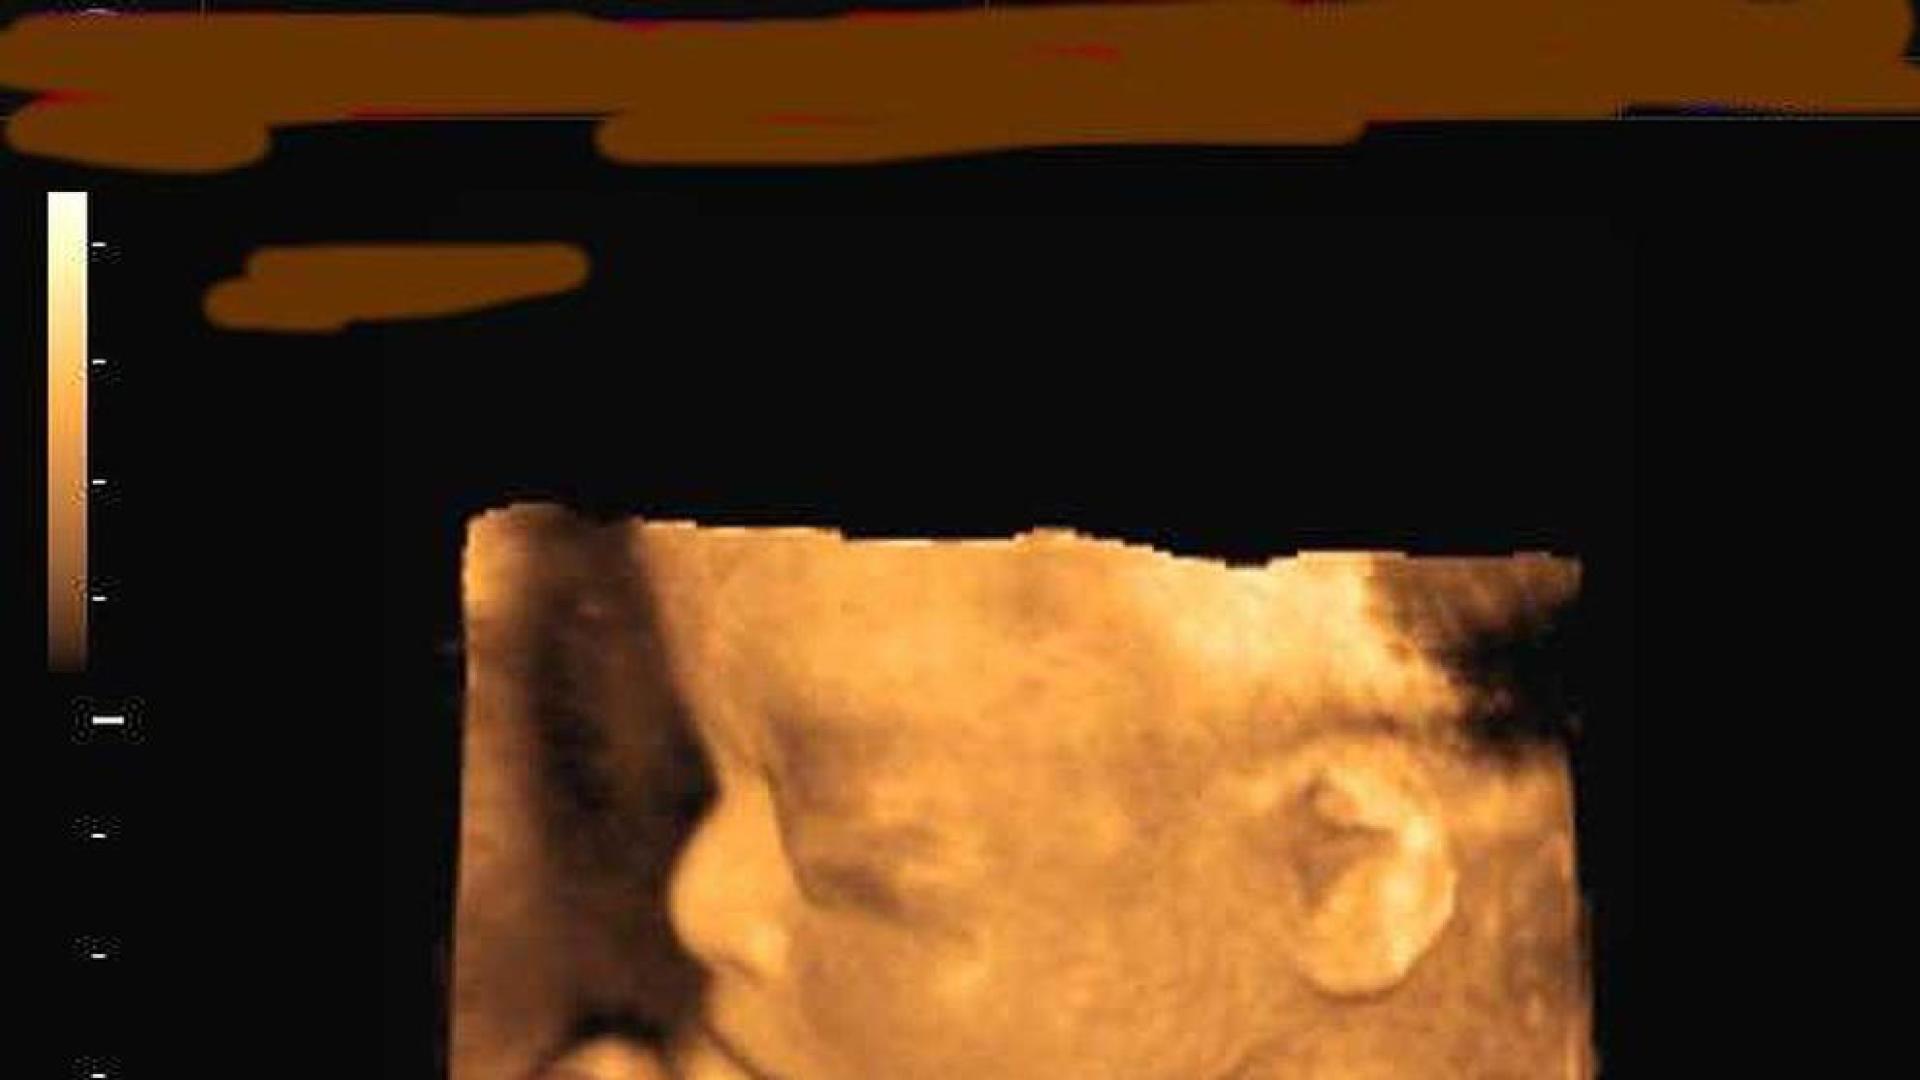

El sistema visual de los bebés es inmaduro al nacer pero hay una parte innata y primitiva que reacciona a la luz y permite que abra los ojos enseguida después del parto

En el segundo trimestre de embarazo, los fetos pueden detectar la luz pero no imágenes. Hasta ahora, se creía que las células sensibles a la luz en la retina en desarrollo eran simples interruptores de encendido y apagado, presumiblemente para establecer los ritmos de día y noche. Sin embargo, científicos de la Universidad de California en Berkeley (Estados Unidos) han encontrado evidencia de que estas células, en realidad, se comunican entre sí como parte de una red interconectada, lo que le da a la retina de los bebés más sensibilidad a la luz de lo que se pensaba.

El sistema visual de los bebés es inmaduro al nacer. Hay una parte innata y primitiva que reacciona a la luz y permite que abra los ojos enseguida después del nacimiento. Sin embargo, otras habilidades visuales las adquiere a lo largo del desarrollo, en especial a lo largo del primer año de vida.